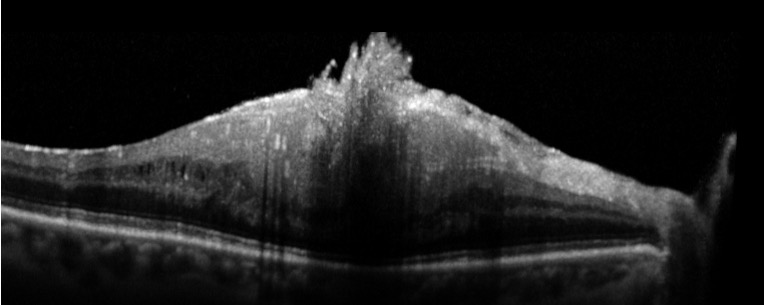

L’OCT pour porter une bonne indication chirurgicale d’un hématome maculaire

Un hématome maculaire peut compliquer une DMLA et entraîner une baisse d’acuité visuelle avec un scotome central important. Si cette hémorragie est récente (< 15jours), elle peut bénéficier d’une chirurgie qui aura pour but de déplacer l’hématome en rétine inférieure. L’OCT va chercher à localiser l’hématome par rapport à l’épithélium pigmentaire. Un hématome principalement sous-rétinien (et non sous l’épithélium pigmentaire) représentera une bonne indication opératoire (figure 9).